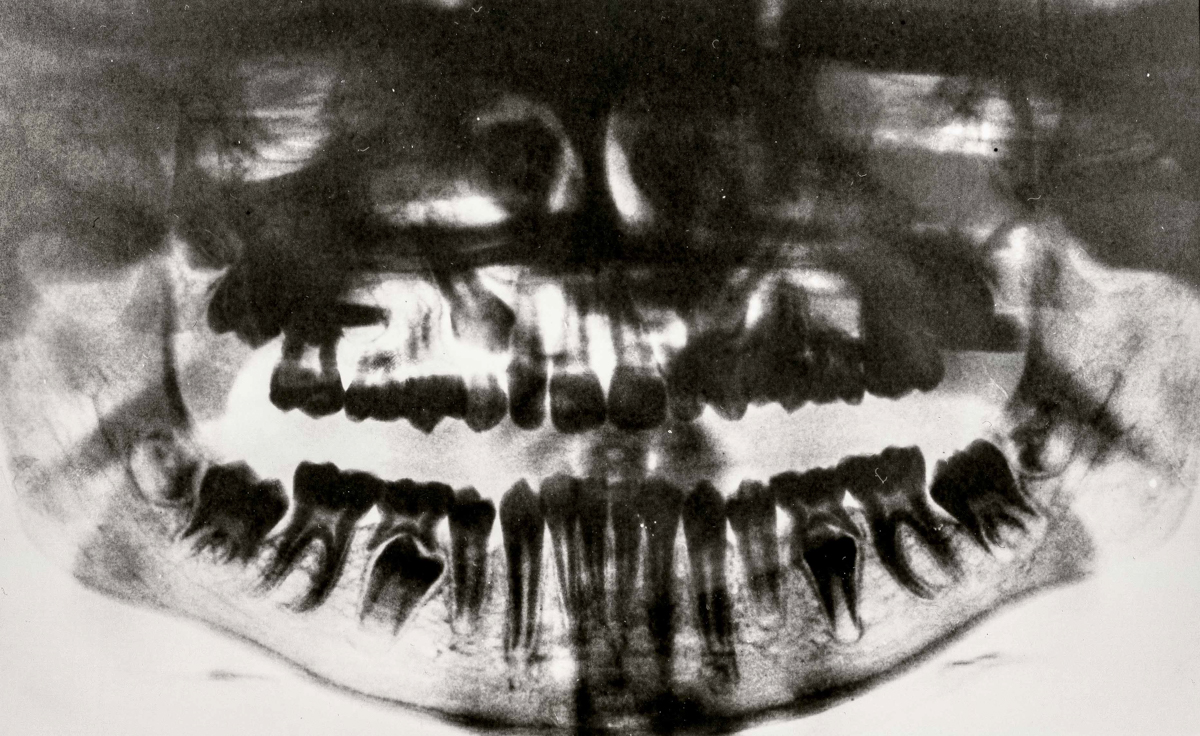

SURFACES SENSIBLES — À la frontière de l'autoportrait, "Surfaces sensibles" retranscrit une partie de ma réalité et brouille les limites entre l'intime anatomique et l'émotionnel.

La science produit les images les plus concrètes et les plus neutres pour illustrer les affects. Pourtant, par leur froideur et leur distance, elles sont les moins aptes à témoigner des émotions. Chaque radiographie, scanner, IRM correspond à une douleur ou à un mal-être spécifique.

Depuis peu, ces images ne sont plus seulement des réminiscences de douleurs passées, mais également des matériaux bruts inspirants pour ma pratique photographique. À partir des radios originelles, j'ai utilisé plusieurs techniques telles que la superposition et le tirage argentique dans le but de me rapprocher d'une perception alternative de ce corps irradié.